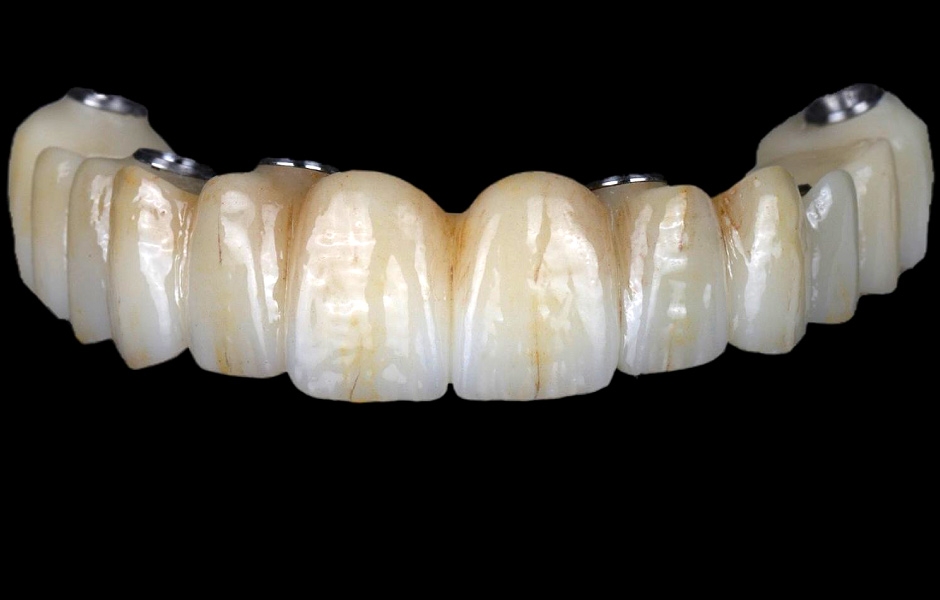

Pro kotvení definitivní náhrady byly použity abutmenty Variobase® for Bridge. Materiálem pro výrobu definitivní náhrady byl zvolen monolitický zirkon (obr. 49, 50).

Obr. 49

Obr. 50